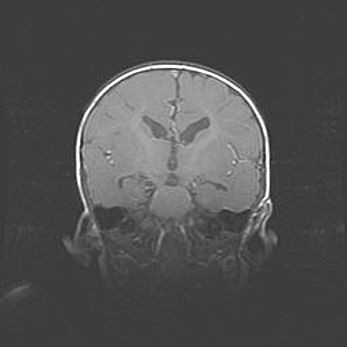

Церебральная ишемия II.

Возраст: 5 дней

Вес: 3400 г

Пол: женский

Окружность головы: 35 см

Срок гестации: 39 недель

Церебральная ишемия – это заболевание, характеризующееся недостаточностью (гипоксией) либо полным прекращением (аноксией) снабжения мозга кислородом по причине закупорки одного или нескольких сосудов. Это приводит к  что метаболическим расстройствам различной степени тяжести в тканях головного мозга, развитию коагуляционных некрозов и гибели нейронов.